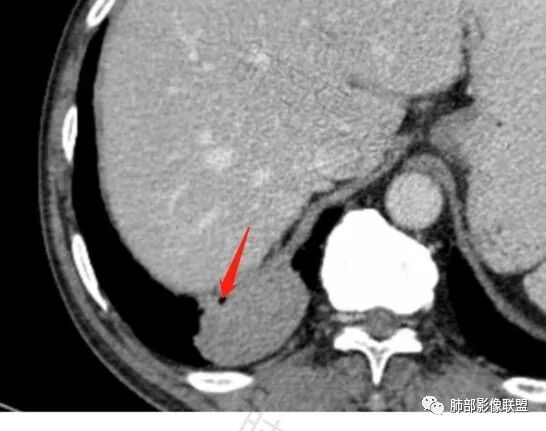

这条血管哪里来的?需要交代一下

南边:

这些是什么呢?

含气组织

常规肿瘤如果背侧胸膜来源,肿瘤与胸膜之间不应该夹杂含气支气管,会推移

但是肺内可以将支气管外推,夹在胸膜之间

与膈面胸膜类似推断

支持肺内

但是这条血管需要交代一下:

如果胸壁来源更不一样

肺动脉供血

如果这是同一根肺动脉,支持PSP

因为肺门区来源肺动脉